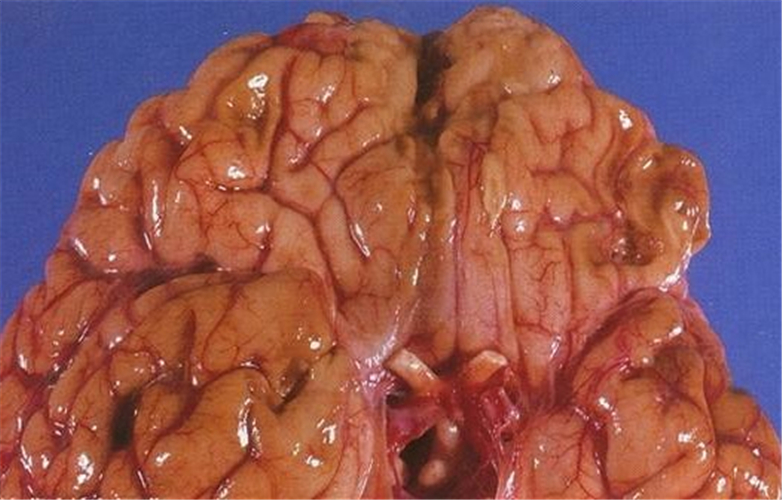

腦梗塞圖片

小腦腦梗塞

外傷性腦梗塞腦部